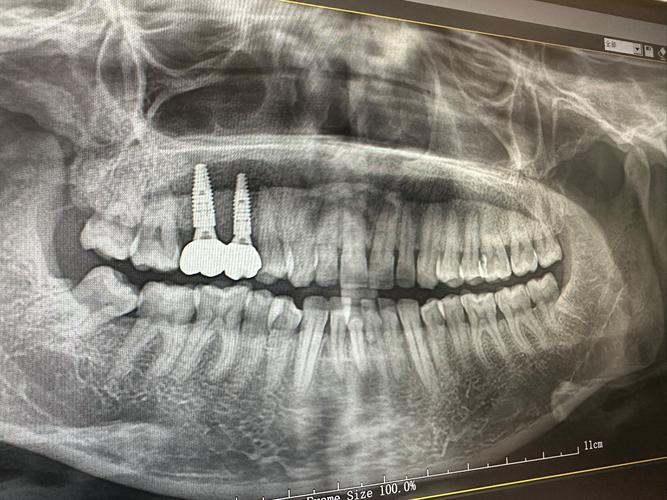

特殊种植体选择

若骨宽度轻度不足或患者不愿接受骨增量手术,可选用特殊种植体:

- 窄直径种植体:直径3.3mm以下,适用于前牙区或后牙轻度骨量不足,避免复杂骨增量手术,缩短疗程,但承重力相对较小,不适用于后牙区大负荷。

- 平台转移设计种植体:通过减小基台直径,减少边缘骨吸收,增加长期稳定性,适合轻中度骨宽度不足,但对种植系统要求高。

- 倾斜种植技术:将种植体植入邻牙牙根之间,避开骨量不足区域,利用邻牙骨支持,适用于后牙区骨量不均的情况,需精准设计,避免影响修复体美观。

术前需通过CBCT精确测量牙槽骨宽度、高度、密度,评估骨量情况;选择经验丰富的口腔种植医生,制定个性化方案;术后保持口腔卫生,避免种植区咀嚼硬物,遵医嘱服用抗生素和止痛药;定期复查,监测种植体周围骨情况及咬合功能,确保长期稳定。